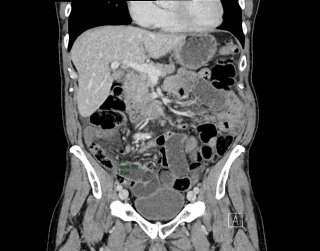

Case presentation

A 31-year-old previously healthy woman, with no surgical history, presented with sudden-onset, severe peri-umbilical abdominal pain unresponsive to high-dose opioids. CT-scan revealed mildly dilated distal jejunum with mesenteric edema and free fluid (Fig. 1, 2). Because of persistent pain despite step III analgesia, emergency diagnostic laparoscopy was performed. Intraoperatively, a closed-loop obstruction of an ileal segment was identified, herniated through a narrow internal window formed by an adherent mesenteric vessel supplying a Meckel’s diverticulum (Fig. 3). The vascular band was divided, releasing the closed loop, with no irreversible small bowel ischemic damage. The Meckel’s diverticulum was resected. The post-operative course was uneventful, and the patient was discharged after two days.